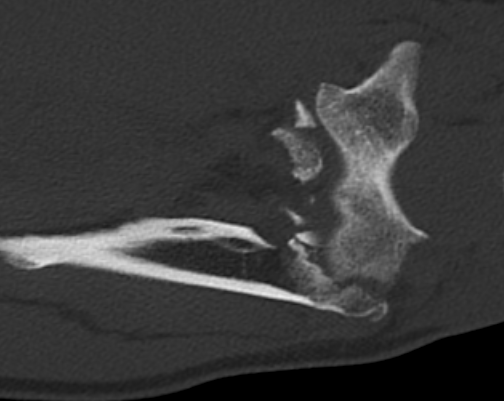

Orthopedic Surgeon with special interest in joint preservation